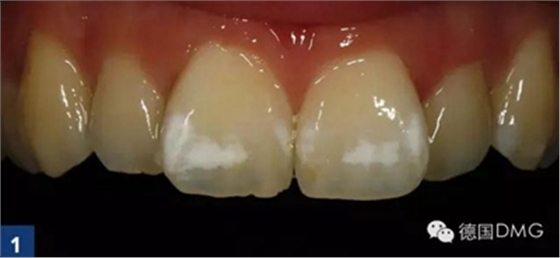

案例1:輕度氟斑牙

作為日常檢查的一部分,患者強(qiáng)烈要求對(duì)前牙區(qū)的白色斑塊進(jìn)行治療(Fig. 1). 權(quán)衡比較了多種治療方案后, 患者和我們共同選擇了滲透治療。

經(jīng)大量研究和證據(jù)表明,滲透治療是最適合用于牙正畸后由于牙釉質(zhì)脫礦造成的白斑病變。根據(jù)患者的居住地區(qū)和成長經(jīng)歷以及白斑的表現(xiàn)形式,我們將位于牙位11和21的唇面白斑診斷為氟牙癥指數(shù)0.5(根據(jù)Dean的社區(qū)氟牙癥指數(shù)).